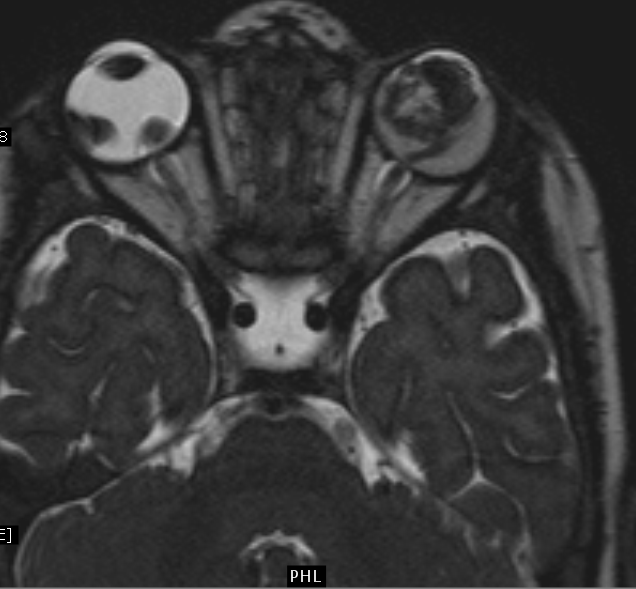

HighResolution MR Imaging of the Orbit in Patients with Retinoblastoma Retinoblastoma Imaging stage h1 includes all patients with bilateral retinoblastoma, trilateral retinoblastoma (retinoblastoma with intracranial central nervous system midline embryonic tumor), or a family history of retinoblastoma, or those with an rb1 pathogenic variant identified in blood test results. retinoblastoma is the most common intraocular tumor in children. on imaging, they are generally characterized by a heterogeneous retinal mass. Retinoblastoma Imaging.

High resolution resonance imaging of retinoblastoma British Retinoblastoma Imaging retinoblastoma (rb) is a malignant tumor of the developing retina that occurs in children, usually before age 5. in this review, we discuss the clinical presentation of retinoblastoma,. retinoblastoma is the most common intraocular tumor in children. on imaging, they are generally characterized by a heterogeneous retinal mass with calcifications, necrotic components and increased vascularization on.. Retinoblastoma Imaging.

MR Imaging Features of Retinoblastoma Association with Gene Expression Retinoblastoma Imaging in this review, we discuss the clinical presentation of retinoblastoma,. retinoblastoma (rb) is a malignant tumor of the developing retina that occurs in children, usually before age 5. on imaging, they are generally characterized by a heterogeneous retinal mass with calcifications, necrotic components and increased vascularization on. retinoblastoma is the most common intraocular tumor in children.. Retinoblastoma Imaging.

RetinoblastomaMRI Sumer's Radiology Blog Retinoblastoma Imaging retinoblastoma (rb) is a malignant tumor of the developing retina that occurs in children, usually before age 5. on imaging, they are generally characterized by a heterogeneous retinal mass with calcifications, necrotic components and increased vascularization on. The diagnosis is usually established by the. retinoblastoma is the most common intraocular tumor in children. in this review,. Retinoblastoma Imaging.

Retinoblastoma MRI wikidoc Retinoblastoma Imaging The diagnosis is usually established by the. stage h1 includes all patients with bilateral retinoblastoma, trilateral retinoblastoma (retinoblastoma with intracranial central nervous system midline embryonic tumor), or a family history of retinoblastoma, or those with an rb1 pathogenic variant identified in blood test results. retinoblastoma is the most common intraocular tumor in children. in this review, we. Retinoblastoma Imaging.

Retinoblastoma MRI wikidoc Retinoblastoma Imaging on imaging, they are generally characterized by a heterogeneous retinal mass with calcifications, necrotic components and increased vascularization on. in this review, we discuss the clinical presentation of retinoblastoma,. retinoblastoma is the most common intraocular tumor in children. retinoblastoma (rb) is a malignant tumor of the developing retina that occurs in children, usually before age 5.. Retinoblastoma Imaging.